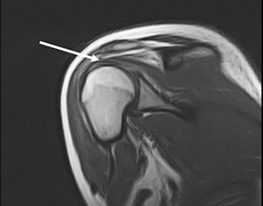

Пациентка 16 обратилась с жалобами на боли в области правого плечевого сустава, усиливающиеся при отведении правой руки кнаружи. При опросе было выяснено, что боль появилась месяц назад во время тренировки в спортзале после падения на область правого плеча. Обратилась за помощью в травмпункт. Пациентке была выполнена рентгенография плечевого сустава, на которой никаких признаков травматического повреждения выявлено не было. С диагнозом ушиб правого плечевого сустава пациентка была отпущена домой. В связи с сохраняющимися болями в суставе, через 2 недели пациентка повторно обратилась за помощью. Ей была выполнена ультрозвуковая диагностика, при которой был выявлен отек тканей области плечевого сустава и незначительный синовит и рекомендовано проведения противовоспалительной терапии. Однако никакого эффекта эта терапия не дала. Нами было проведено МРТ обследование, при котором было выявлено повреждение надостной мышцы – указано стрелкой (см. фото).

Пациентке было выполнено оперативное восстановление поврежденной мышцы. Через 8 недель после операции пациентка смогла полноценно без боли пользоваться правой рукой